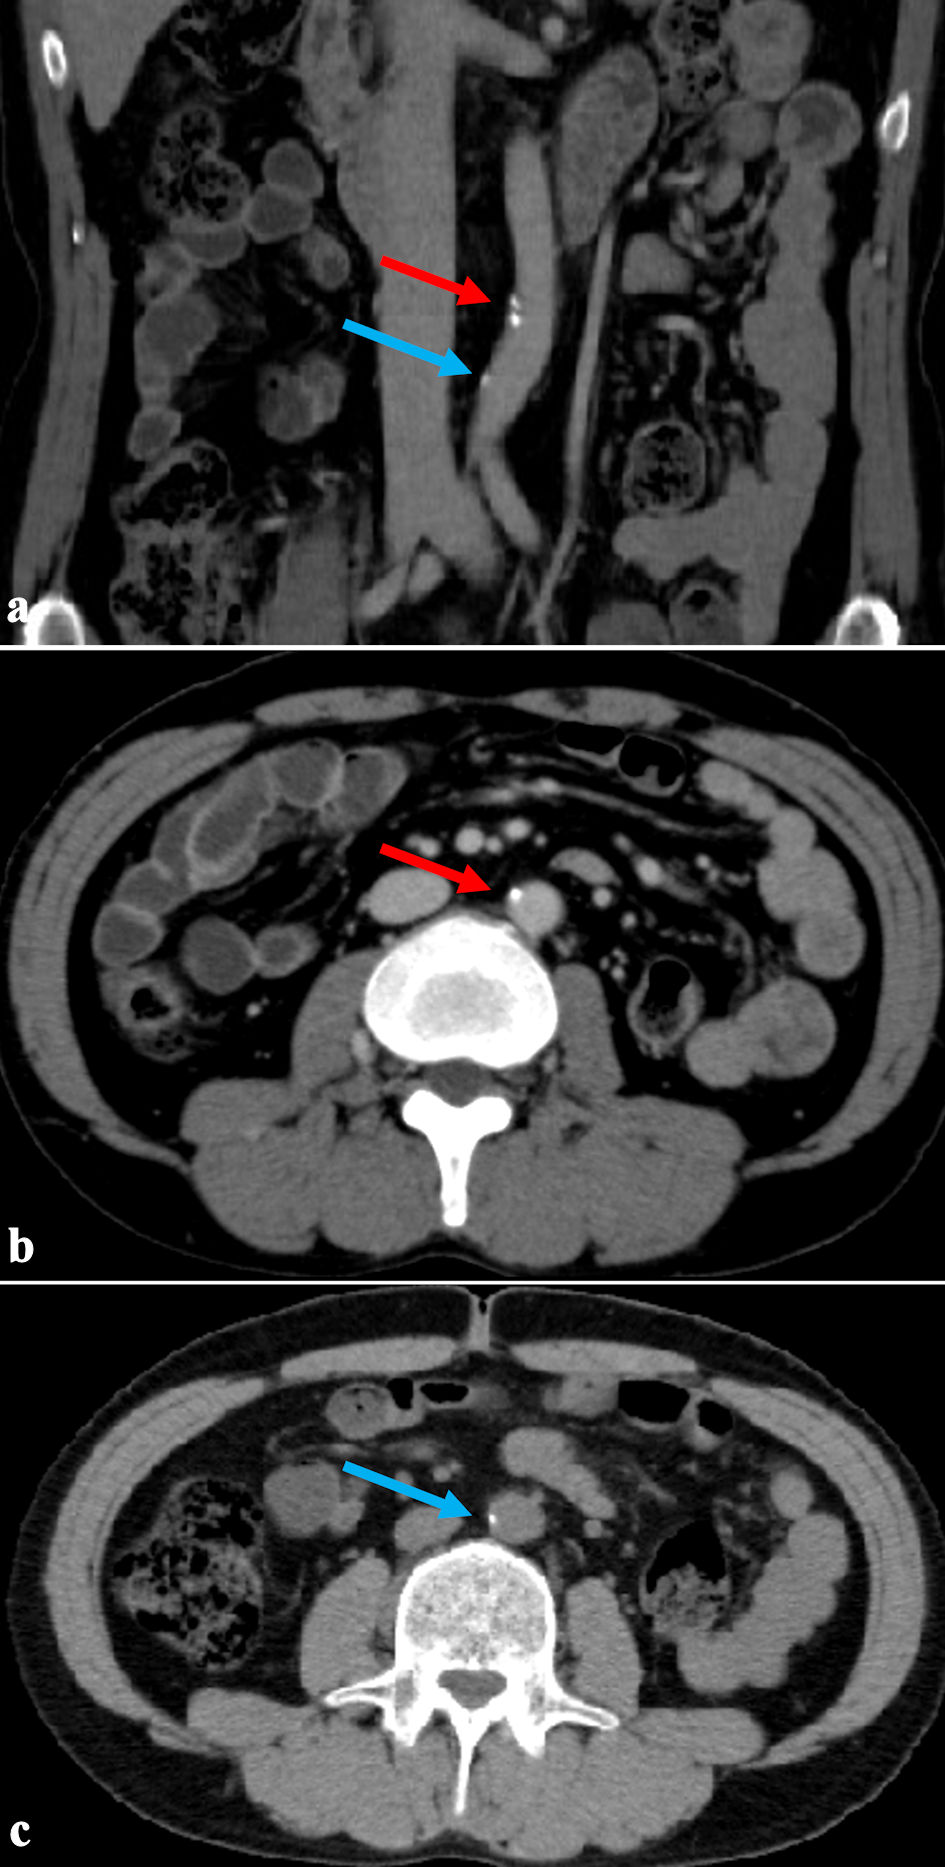

Click for large image

Figure 2. The first abdominal CT scan 29 years after the initiation of dialysis (age 53). (a) Coronal section. (b, c) Axial sections showing abdominal aortic calcification area. The red arrow indicates the upper calcification area, and the blue arrow indicates the lower area. Despite undergoing 29 years of long-term dialysis, calcification remained slight. CT: computed tomography.

A CT scan performed 29 years after initiating hemodialysis revealed vascular calcification in the abdominal aorta; however, the AACI was low at 5.8%. Five years later, the AACI increased slightly to 6.7%; however, no new vascular calcifications were observed in the thoracoabdominal aorta during these 5 years (Fig. 3b, c). However, calcification of the internal iliac artery was found, but there was no evidence of buttock claudication due to impaired blood flow in the internal iliac artery (Fig. 4).